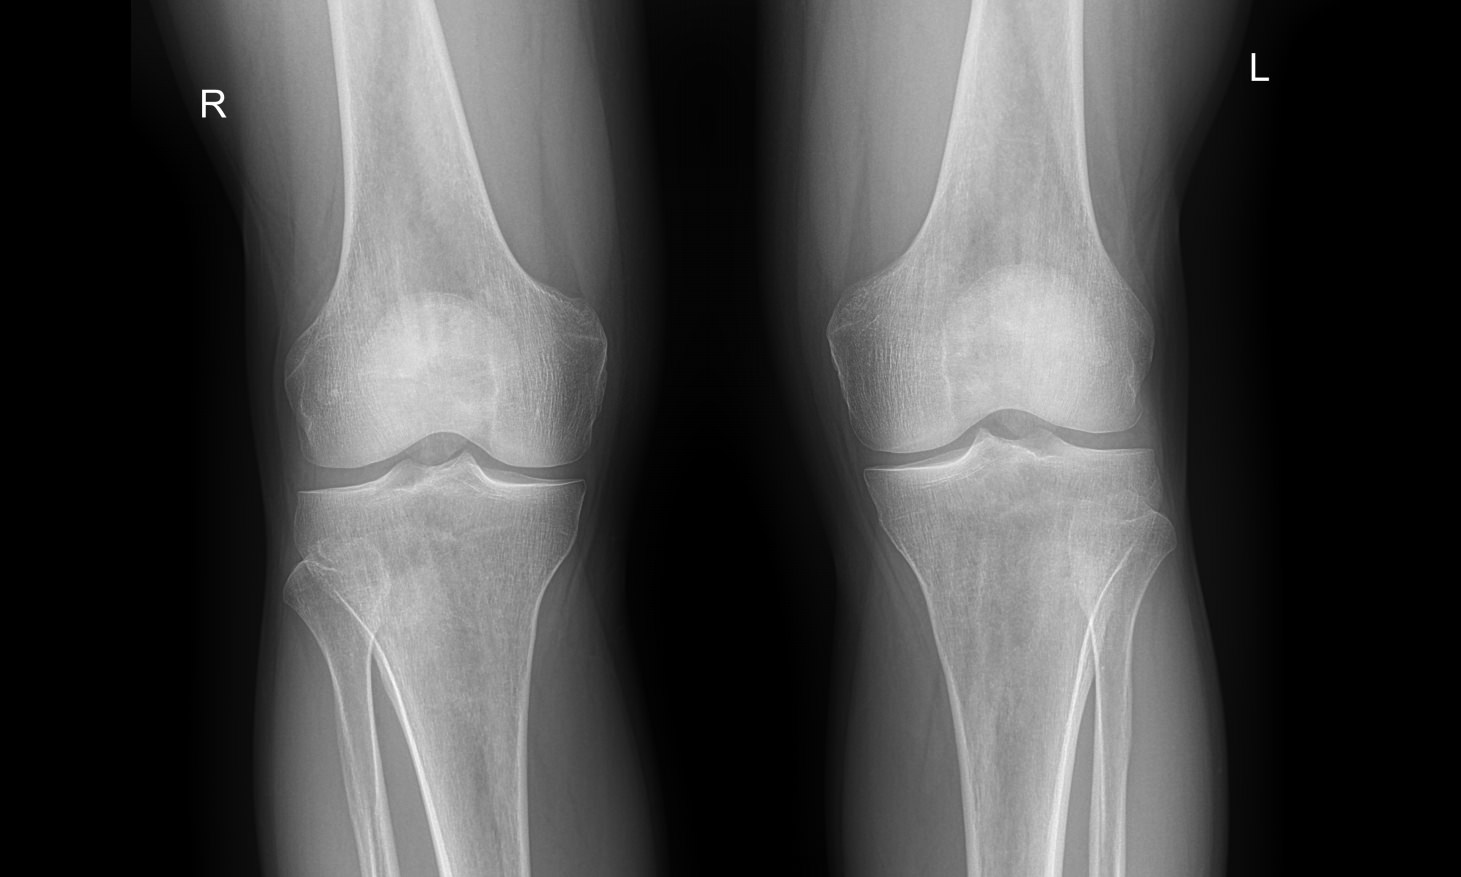

Что покажет рентген обоих коленных суставов в одной проекции

В протоколе у каждого сустава описывается:

• Состояние мягких тканей;

• Суставная щель ― в норме, расширена, сужена, затемнена, имеет дополнительные включения;

• Состояние суставных  поверхностей и их соответствие друг другу ― несоответствие говорит о вывихе;

• Положение надколенника ― обычное или нет;

• Состояние костной ткани и надкостницы ― могут быть обнаружены участки разрежения, размягчения или других патологических процессов, а также свежие и сросшиеся переломы.